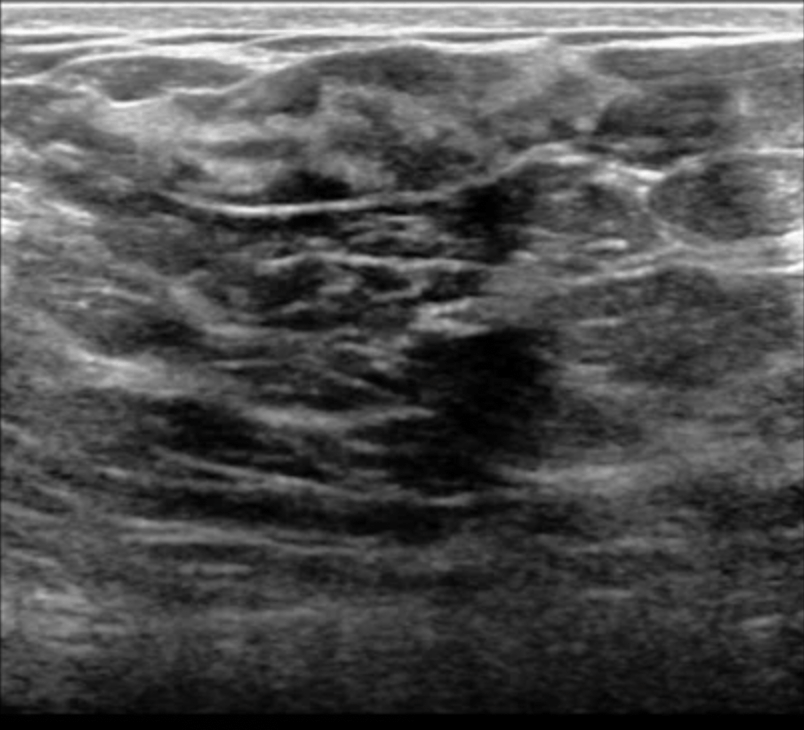

- On ultrasound:

- PASH tends to be:

- An oval, round hypoechoic mass or

- Can presents as a heterogeneous mass with cystic areas

- According to Cohen et al:

- When a focal lesion with well-defined borders, containing no calcifications on mammography or a well-defined hypoechoic mass on ultrasound is seen:

- PASH can be considered and included in the differential diagnosis